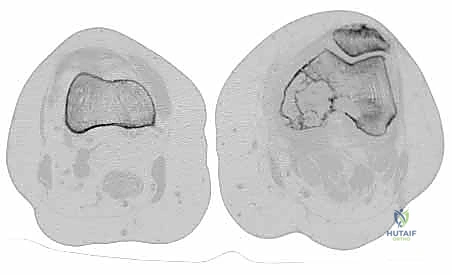

* النقائل الحالة للعظم (Osteolytic): (مثل سرطان الثدي والرئة والكلى) تؤدي إلى تدمير مفرط للعظم، مما يتركه مليئاً بالفجوات وهشاً للغاية وقابلاً للكسر بسهولة.

* النقائل البانية للعظم (Osteoblastic): (خاصة في سرطان البروستاتا) تؤدي إلى تكوين عظم جديد ولكنه عظم عشوائي وضعيف البنية، وهو أيضاً عرضة للكسر.

* النقائل المختلطة: تحتوي على كلا النوعين من التدمير والبناء.

- التصوير المقطعي المحوسب (CT Scan): يقدم تفاصيل ثلاثية الأبعاد لا مثيل لها لجودة القشرة العظمية المتبقية. يساعد الجراح في التخطيط لحجم المسامير أو الصفائح المطلوبة، وتقييم مدى تدمير العظم.